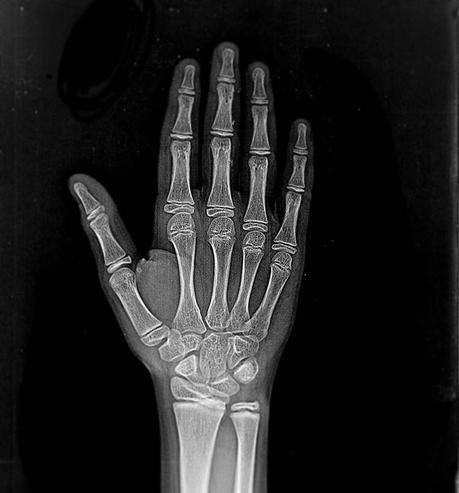

Los rayos X

También son ondas electromagnéticas e ionizantes, prácticamente idénticos a los rayos gamma, pero no son de origen nuclear.

Se producen en un tubo de vacío donde un haz de electrones de un cátodo se dispara contra el material objetivo que comprende un ánodo, por lo que se producen a pedido y no por procesos físicos inexorables.